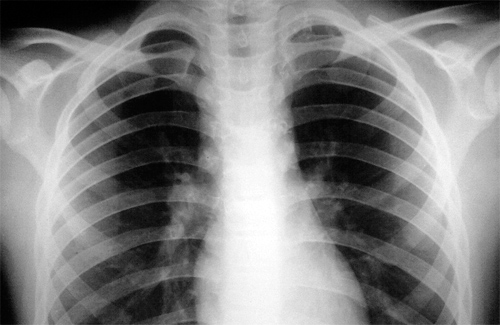

Під час зустрічі, яка відбулась напередодні Дня боротьби з туберкульозом, Оксана Несторівна розповіла, що населення не до кінця розуміє важливість проведення обстеження членів сім’ї вагітної жінки та породіллі. А про необхідність щорічної флюрографії грудної клітки більшість просто забуває. Через це часто туберкульоз виявляється на дуже запущених стадіях. Тому лікарі Центру планування сім’ї регулярно нагадують майбутнім батькам про флюорографію, рентген, щоб перевірити чи є в оточенні вагітної жінки люди із збудником. Адже від цього залежить подальший стан дитини.